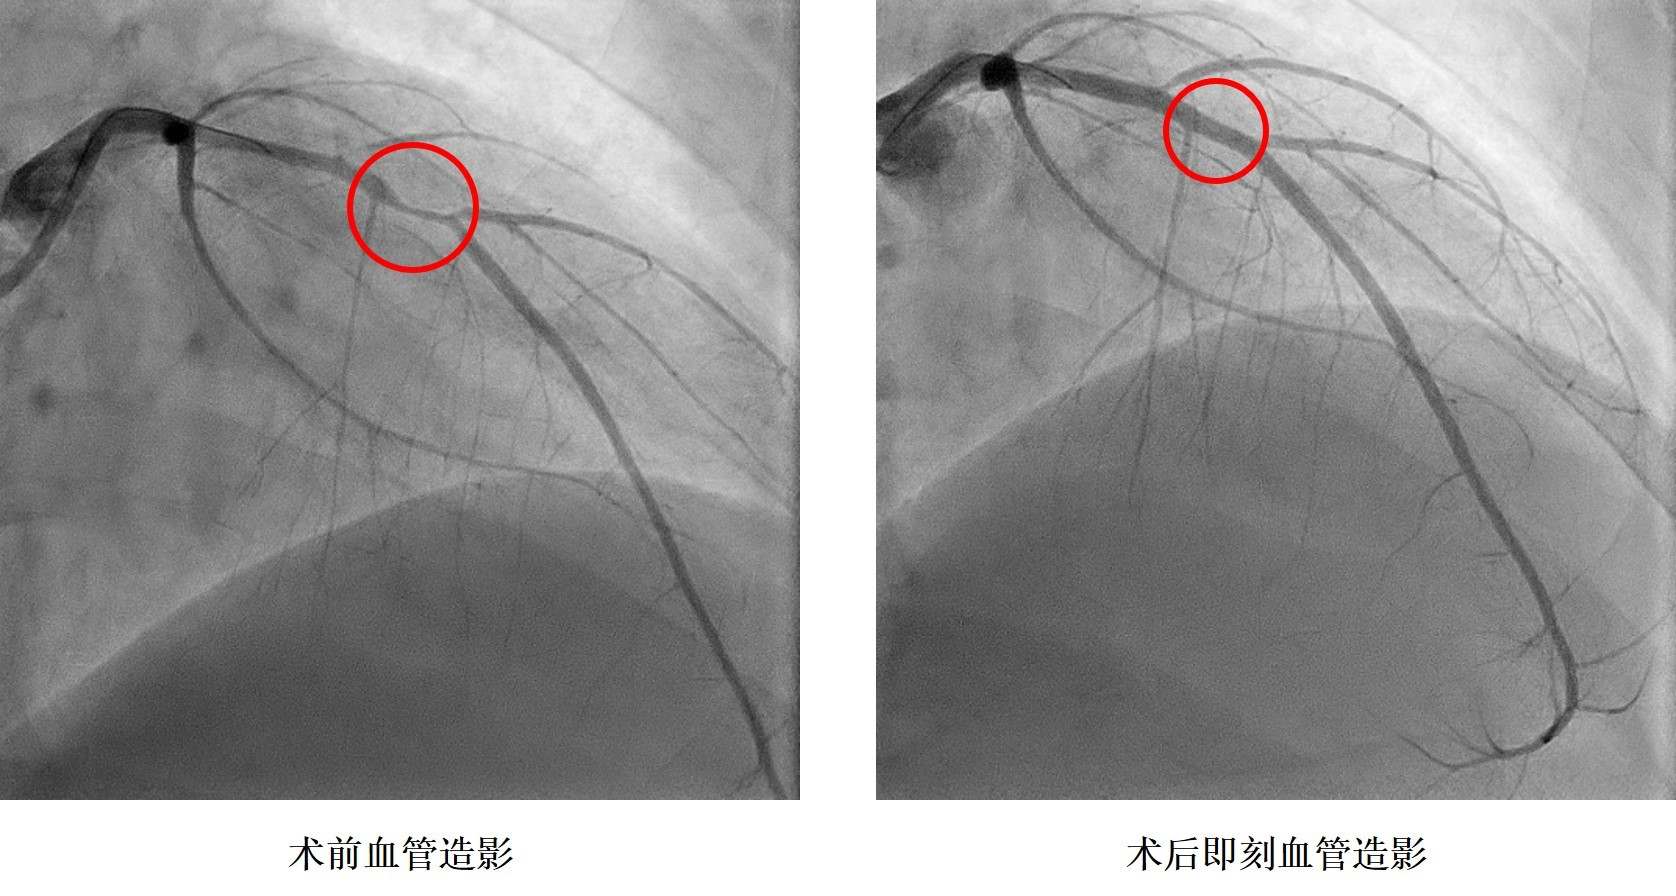

小浩在2019年9月6日晚飯時突感胸痛、胸口悶、呼吸困難,立即前往湖南省人民醫院胸痛中心就診,診斷為急性心肌梗死,小浩被送往介入手術室,進行急診造影后發現冠狀動脈血管嚴重狹窄,需要在體內植入心臟支架。據了解小浩從14歲就開始了抽煙,還發現了高血壓,血壓最高200mmHg,卻一直沒有規律服藥治療。16歲讀完技校后的他開始過上了淘寶電商的生活,生活日夜顛倒,夜間修圖、改片,并頓頓燒烤,白天睡覺,缺乏運動,這樣的生活維持了兩年本次。入院后同時發現了糖尿病,這一系列原因是導致小浩發生心肌梗死的罪魁禍首。

孩子還這么小,人生剛剛開始就要帶上心臟支架生活嗎?心內科鄭昭芬主任組織團隊進行了會診,建議植入生物可吸收心臟支架。“我們本來不愿意植入心臟支架,但聽說有一種新型的心臟支架在植入體內后幾年就能降解,就接受了。”在征得小浩本人和家人同意后,心內三科潘宏偉主任利用血管內超聲指導,順利植入生物可吸收心臟支架,拆除了小浩體內的“炸彈”。